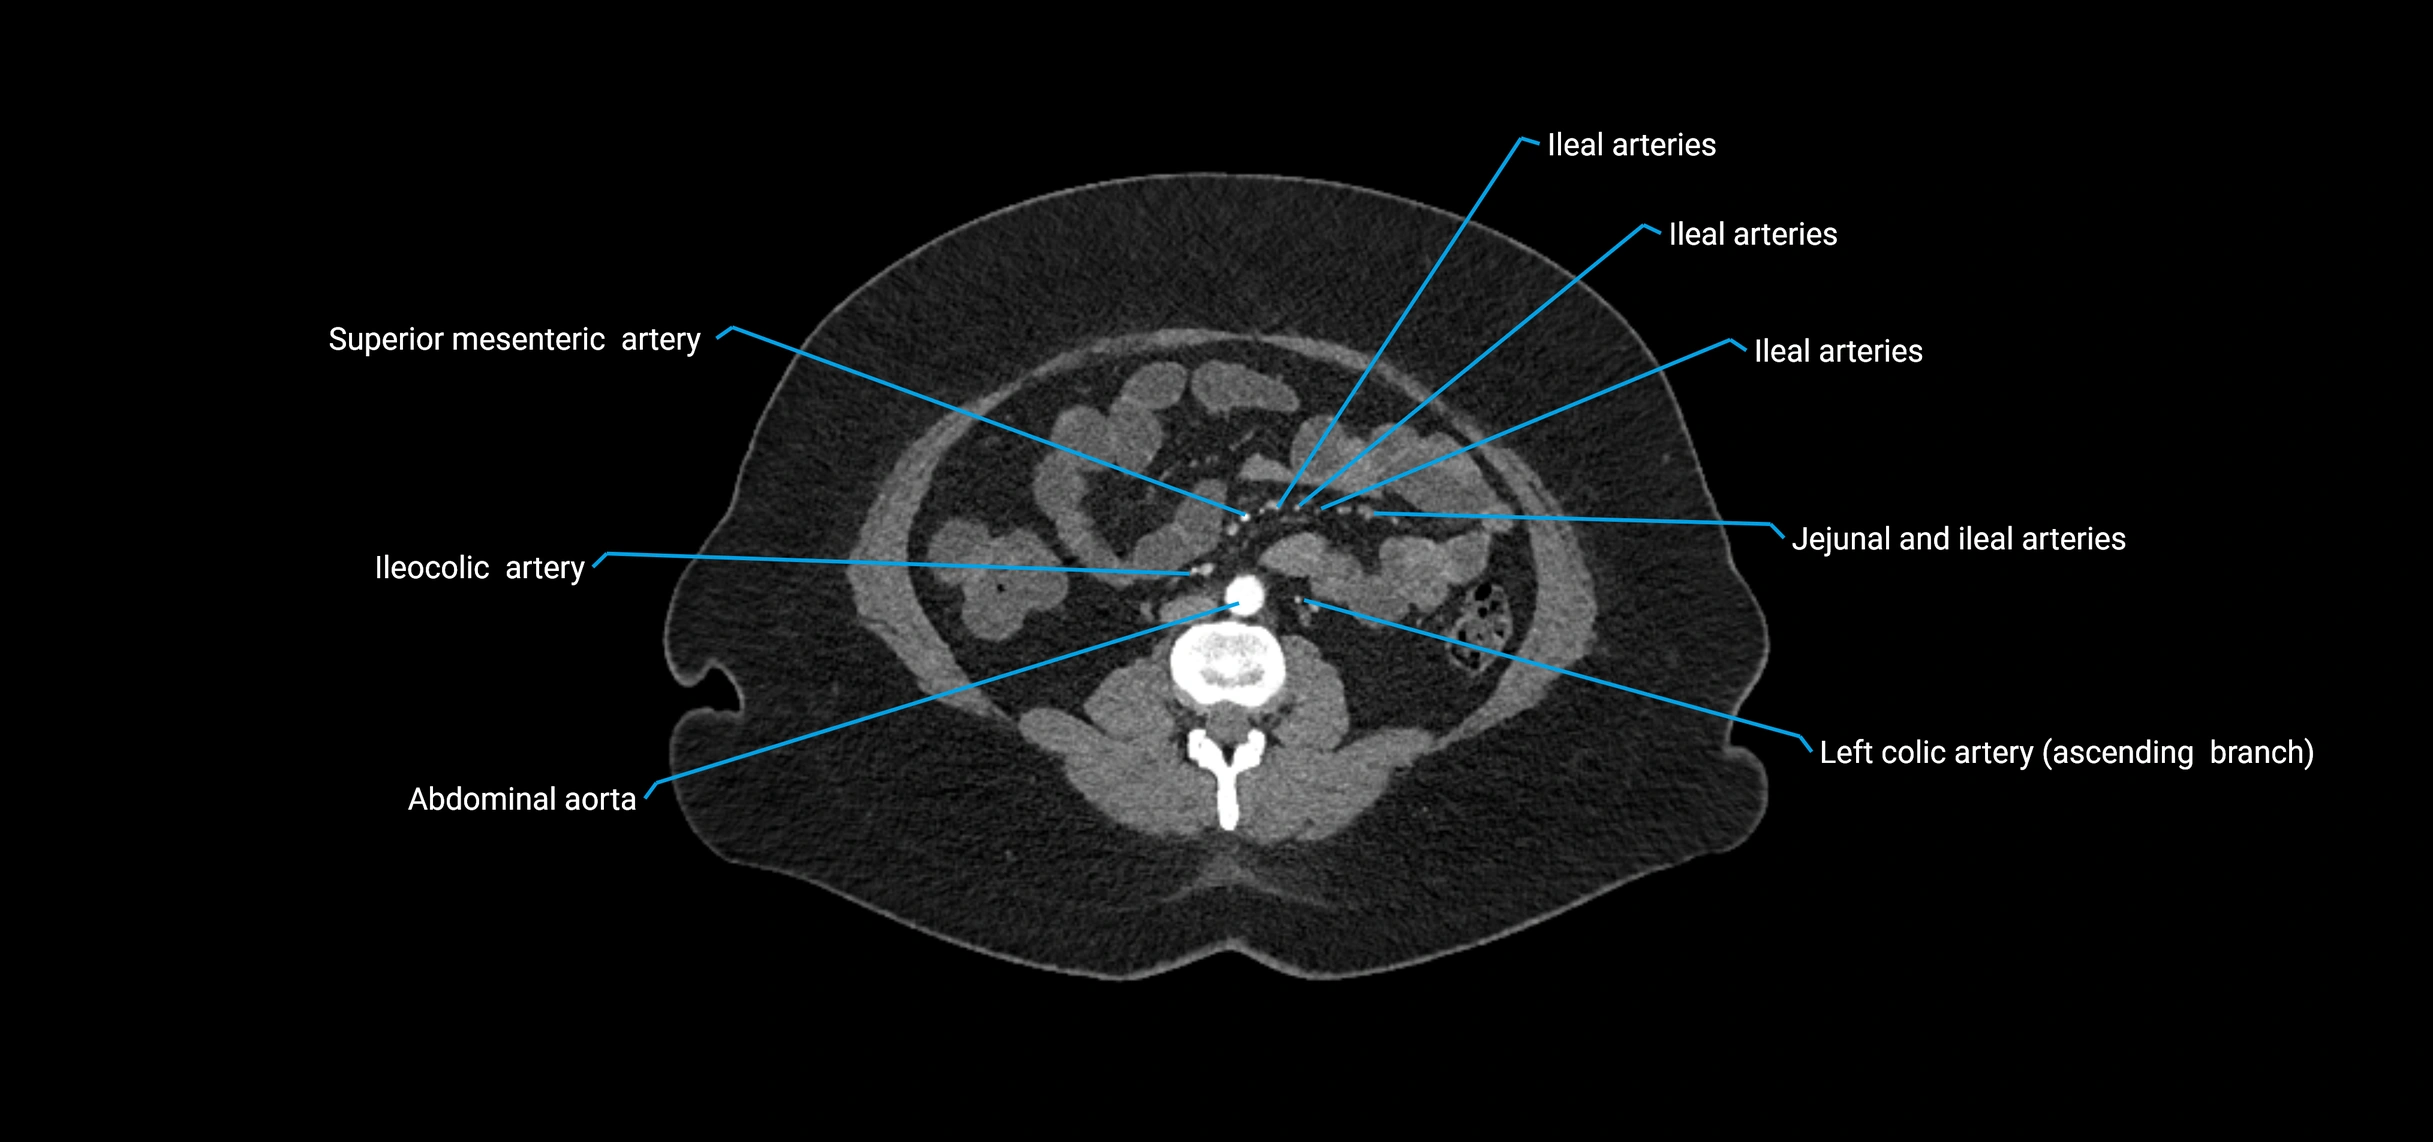

Contrast-enhanced CT (CTA):

• Gold standard for abdominal aortic imaging

• Provides excellent detail of lumen, wall, aneurysm, thrombus, and branch vessels

• Multiplanar and 3D reconstructions help in aneurysm measurement, stent graft planning, and dissection evaluation